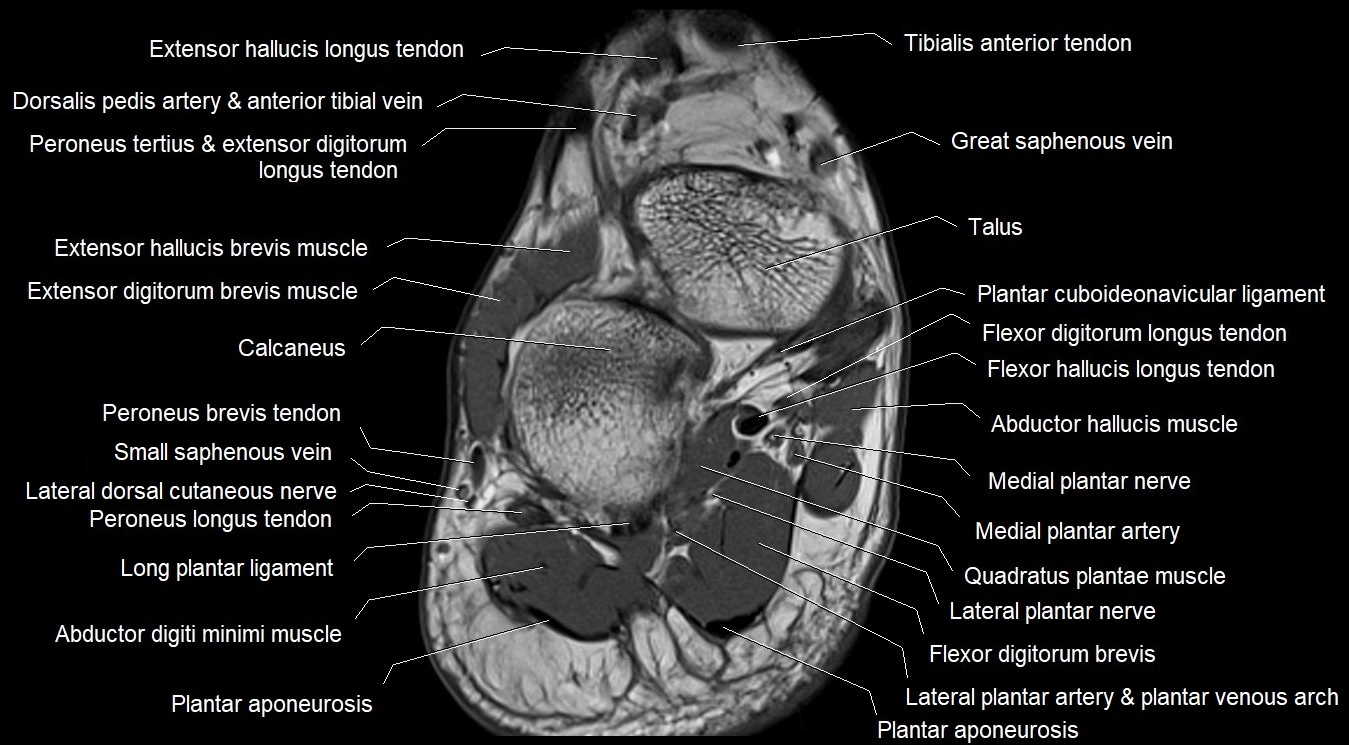

MRI image